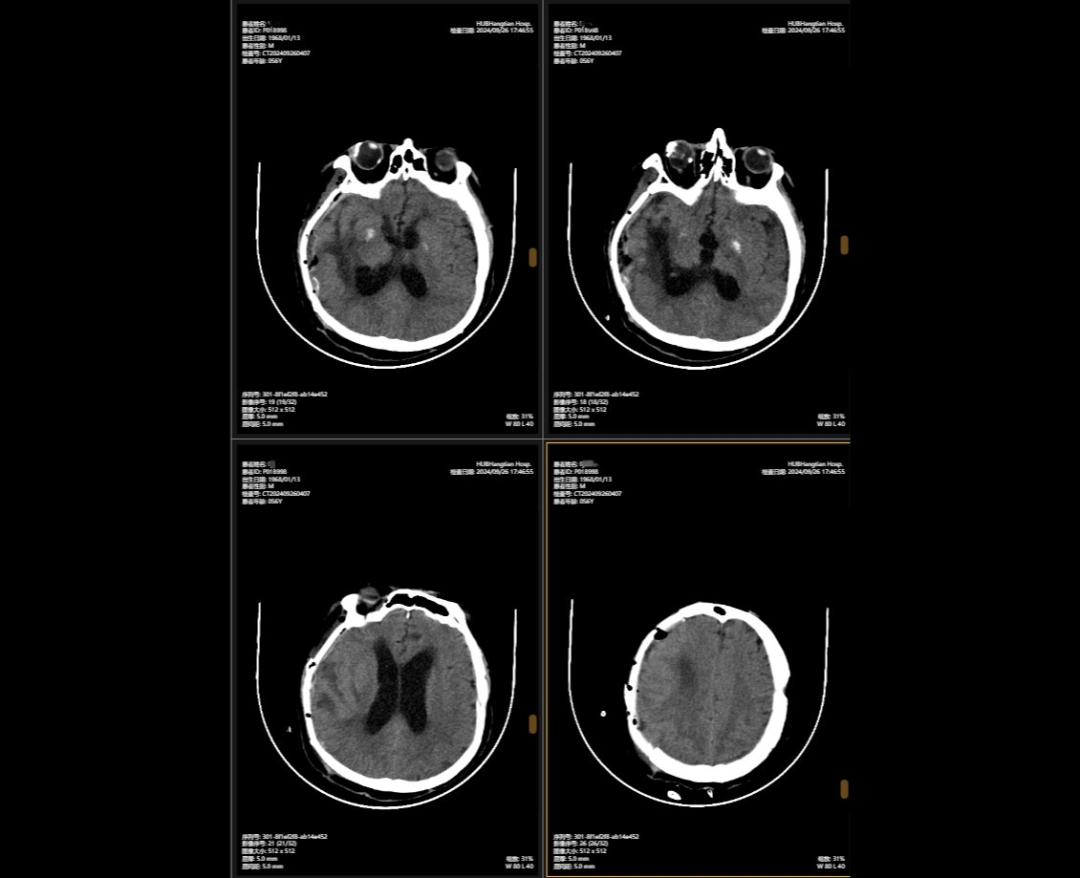

顱骨缺損修補(bǔ)術(shù)前術(shù)后對(duì)比

2024年5月,56歲的李先生(化名)不幸遭遇嚴(yán)重車禍,當(dāng)場(chǎng)昏迷,生命垂危。他被緊急送往湖北航天醫(yī)院后,檢查結(jié)果讓所有人心頭一緊:他的頭部受到嚴(yán)重撞擊,不僅有多處出血,腦組織也有挫傷,甚至連呼吸心跳的“總司令部”——腦干都受了傷。除此之外,還有顱骨、頸椎和多處肋骨骨折,情況萬(wàn)分危急。

李先生頭部的多處損傷就像一顆顆“炸彈”,隨時(shí)可能危及生命。航醫(yī)神經(jīng)外科團(tuán)隊(duì)接診后,面對(duì)如此復(fù)雜的顱內(nèi)損傷,神經(jīng)外科主任陳義勇當(dāng)機(jī)立斷,一方面做好周密的手術(shù)準(zhǔn)備,一方面迅速展開(kāi)多學(xué)科會(huì)診,多學(xué)科團(tuán)隊(duì)緊急集合,反復(fù)協(xié)商探討,一同制定了詳盡手術(shù)方案。手術(shù)方案確認(rèn)后,神外團(tuán)隊(duì)爭(zhēng)分奪秒,第一時(shí)間為李先生實(shí)施了顱內(nèi)多發(fā)血腫清除術(shù)+右側(cè)開(kāi)顱顱內(nèi)減壓+去骨瓣減壓術(shù)+左側(cè)硬膜外血腫清除術(shù)+矢狀竇破裂止血術(shù)。手術(shù)過(guò)程中,醫(yī)生們精準(zhǔn)操作,成功止住了出血,最大限度地保護(hù)了正常腦組織,為李先生贏得了生的希望。

李先生的病情穩(wěn)定后,神外團(tuán)隊(duì)緊繃了數(shù)周的神經(jīng)終于得以松弛,他們隨即為他制定了顱骨缺損與腦積水治療方案,2024年9月,李先生接受了顱骨缺損修補(bǔ)術(shù),“修補(bǔ)”之前取下的頭骨,保護(hù)大腦,解決顱內(nèi)壓力不穩(wěn)問(wèn)題,術(shù)后他的神經(jīng)紊亂癥狀明顯改善;三個(gè)月后,神外團(tuán)隊(duì)繼續(xù)施行腦室-腹腔分流術(shù),通過(guò)植入的分流管,解決了腦積水問(wèn)題,讓腦壓恢復(fù)正常。